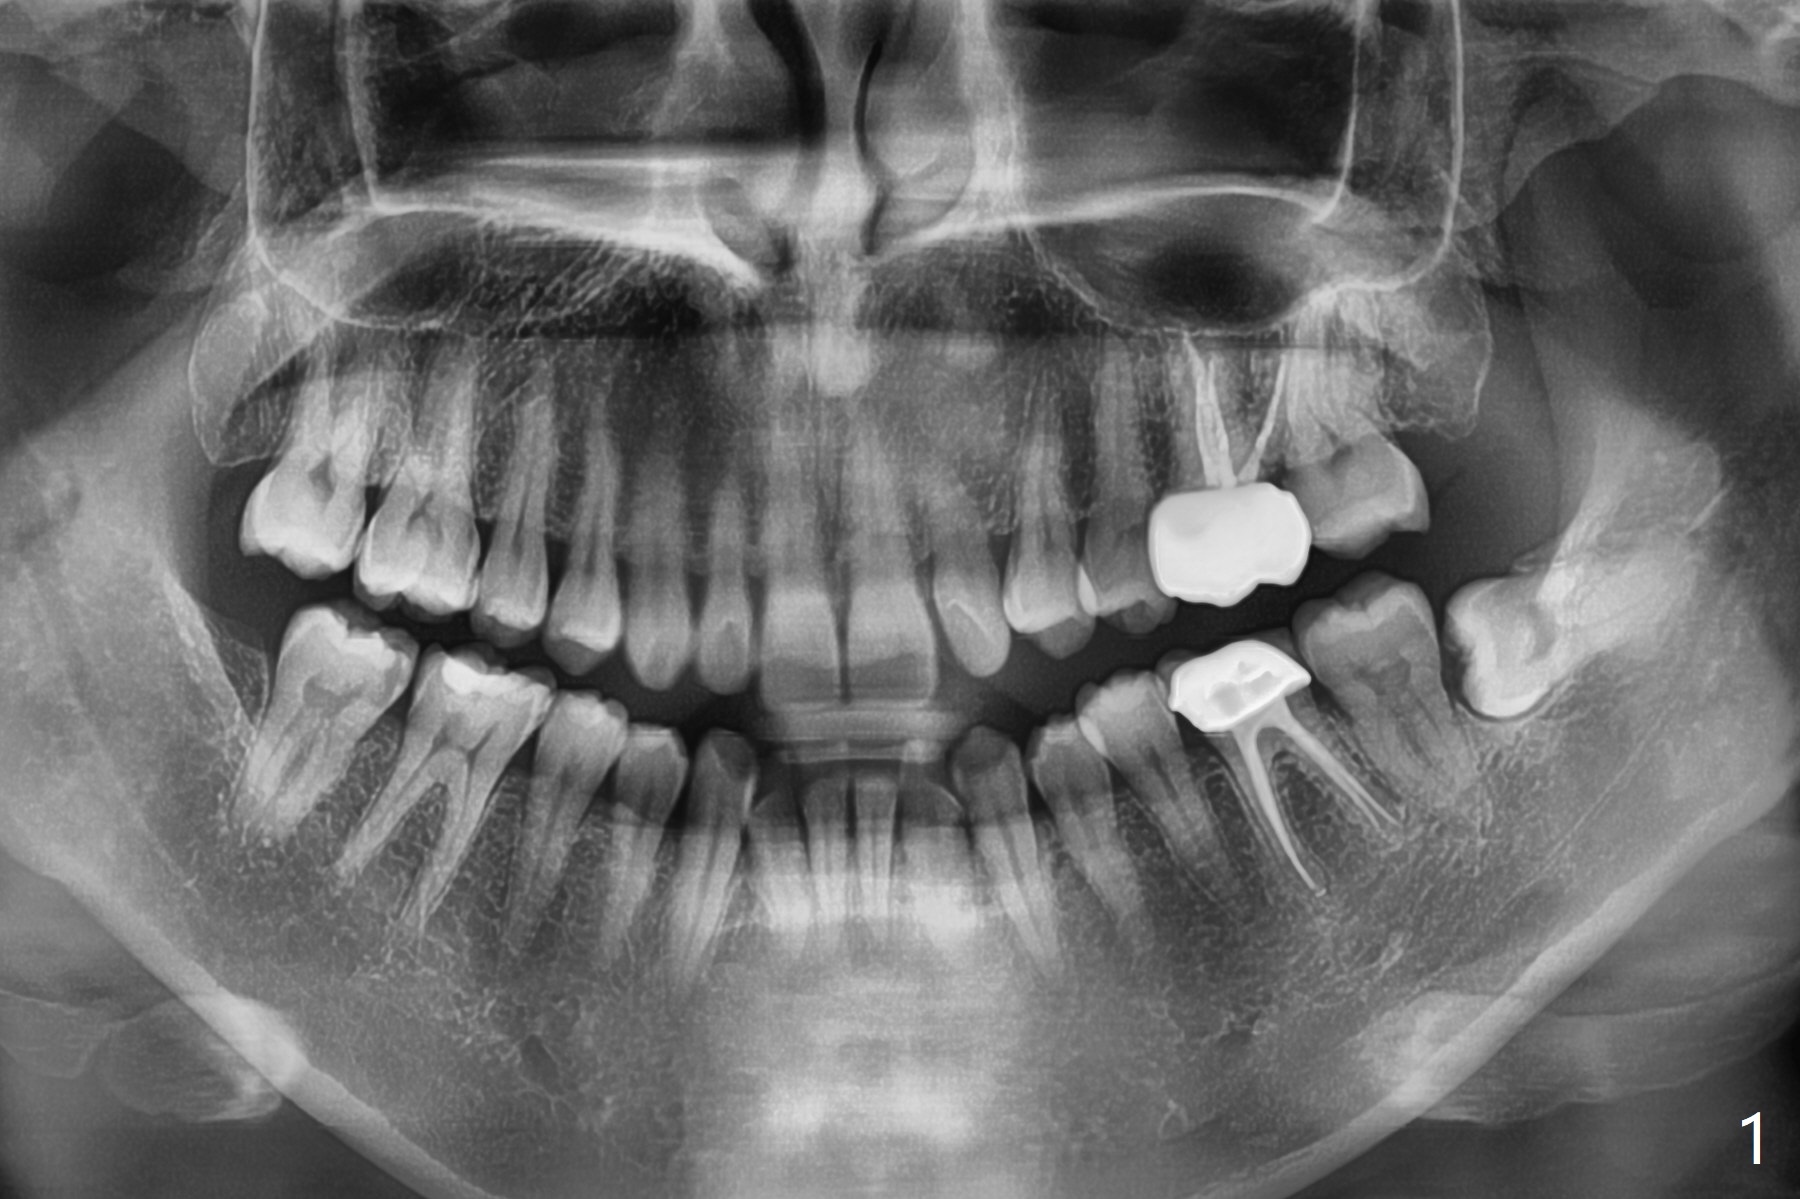

A 41-year-old woman (dental phobic) requests extraction of the tooth #17 because of food impaction (Fig.1). The fractured root tip (Fig.2 *) is so deep that the longest surgical length fissure bur can not reach in spite of multiple sectioning. The nervous patient agrees not to remove the root tip because of pain associated with root tip loosening. The fractured bur tip cannot be found clinically. CBCT should have taken for bur location and the proximity of the root tip to the Inferior Alveolar Canal. To prevent dry socket, Osteogen Plug is placed in the radicular portion of the socket (Fig.3 O), while allograft (A) in the coronal part of the socket. With Collagen Plug placed superficial to the allograft, 4-0 plain gut suture is used to close the socket. The patient returns 11 days postop with chief complaint of "pain returns for 2 days, affecting sleep. Small particles came out". #17 gingiva is healthy, although there is tenderness on deep palpation of #17 D. There is no exudate. Chlorhexidine irrigation is done with 2 syringes with pain relief. Augmentin is prescribed for 7 days. Pain disappears in ~ 1 month. Bone fills the socket 1 year postop (Fig.4).